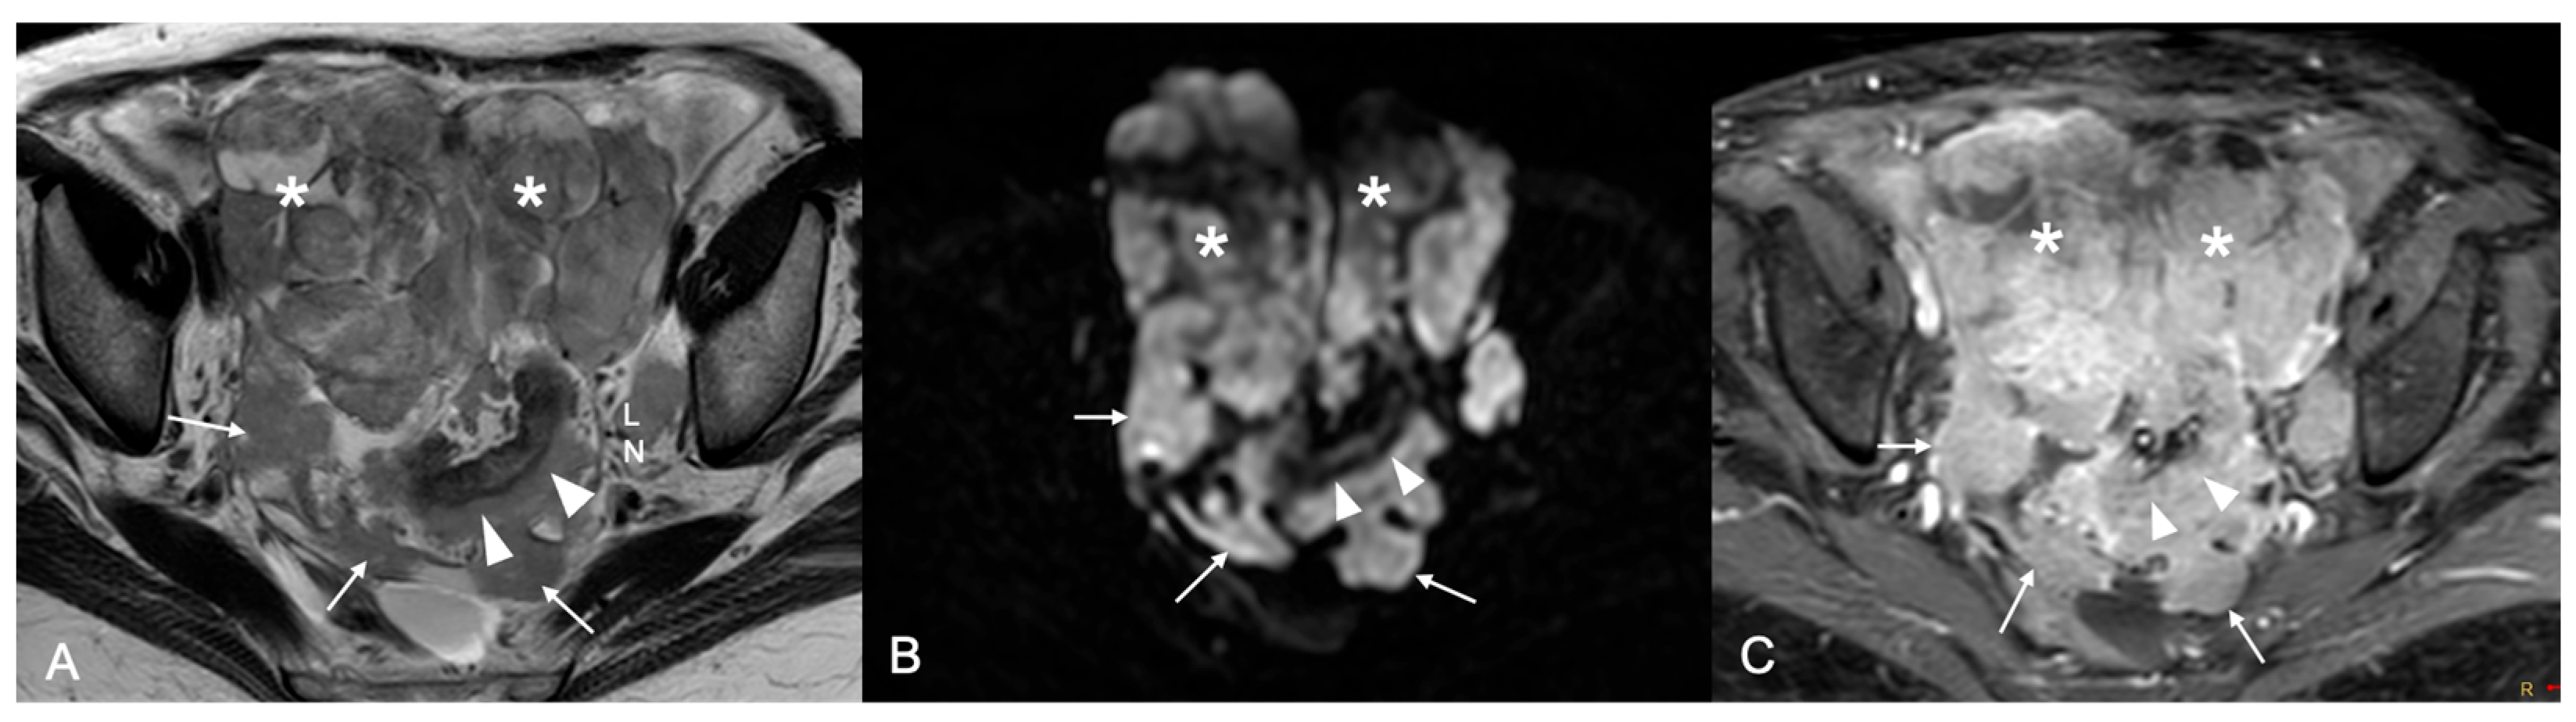

Background/Objectives: Cytoreduction status is a critical prognostic factor in ovarian cancer, yet preoperative selection of patients suitable for primary debulking surgery and accurate prediction of surgical outcome remain challenging. This study aimed to evaluate the prognostic ability of MRI-based Fagotti score and Peritoneal Cancer Index (PCI) for predicting resectability of peritoneal disease in ovarian cancer patients. Methods: This was a prospective single-center observational study. Patients with suspected primary ovarian cancer who underwent preoperative MRI of the abdomen and pelvis with a dedicated protocol were considered. MRI-based Fagotti score and PCI were determined by two readers independently, using a combination of T2W, Diffusion-Weighted Imaging (DWI), and contrast-enhanced T1W sequences. In cases of discordance, a third radiologist reviewed the scans and consensus was reached. ROC analysis and logistic regression were used to evaluate prognostic performance. The reference standard to predict resectability was optimal cytoreduction defined as residual disease ≤1 cm. Results: Forty-six women with epithelial ovarian cancer (mean age 56.3 ± 2.6 years) who underwent preoperative MRI, followed by laparoscopy and/or laparotomy, were included in the study. Both MRI-based Fagotti score and PCI showed high predictive value for predicting resectability (AUC 0.92 and 0.94, respectively). Optimal cut-offs were ≤6 for Fagotti score and ≤20 for PCI. Patients with scores below these thresholds had >60-fold (Fagotti) and >100-fold (PCI) increased odds for successful primary cytoreduction (p < 0.001). Conclusions: MRI-based Fagotti score and PCI may serve as powerful noninvasive predictors of surgical outcome in ovarian cancer. MRI may reliably guide treatment decisions, reducing unnecessary laparotomies and optimizing patient selection.